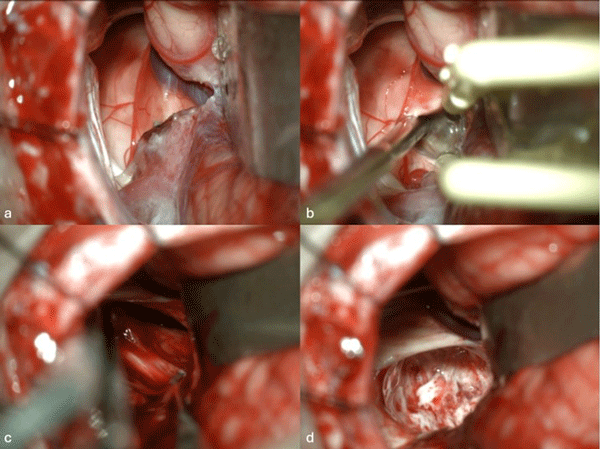

Figura 1. Imágenes intraoperatorias bajo microscopía. Craneotomía suboccipital lateral. Se ingresa al mesencéfalo desde posterior por una ruta supracerebelosa infratentorial lateral. A y B) Corticotomía en surco mesencéfalo lateral. C) Identificación y resección en bloque de la malformación cavernomatosa. D) Revisión del lecho, sin remanente.

Figura 7. Imágenes intraoperatorias bajo microscopía. Abordaje retrosigmoideo ampliado a izquierda, con ruta de ingreso transpedúnculo cerebeloso medio. A) Apertura de fisura horizontal que divide los lóbulos semilunar superior y semilunar inferior del cerebelo, exponiendo el pedúnculo cerebeloso medio. B) Corticotomía en pedúnculo cerebeloso medio, evidenciando la cápsula del cavernoma. C) Resección en bloque de la malformación cavernomatosa. D) Revisión del lecho, sin remanente.